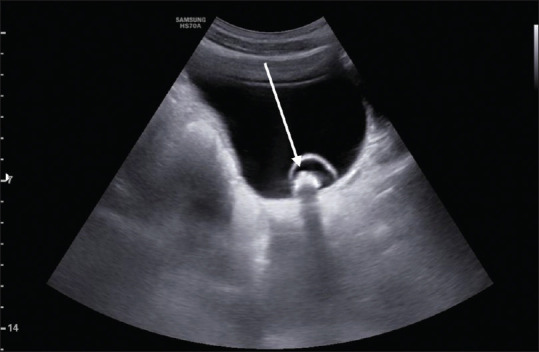

Testicular torsion is an emergency clinical situation. It is rarely seen associated with ureterocele. We presented a case report where a 15-year-old adolescent boy presented with severe testicular and vague abdominal pain was found on imaging to have testicular torsion and ureterocele. Ultrasonography Doppler and computed tomography imaging are being described.

睾丸扭转是一种紧急的临床情况。它很少与输尿管囊肿合并。我们提出一个病例报告,一个15岁的青春期男孩表现为严重的睾丸和模糊腹痛,在影像学上发现有睾丸扭转和输尿管膨出。介绍了超声多普勒和计算机断层成像。